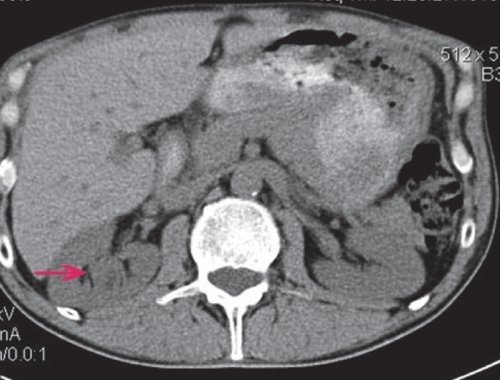

Компьютерная томография

При КТ выявляется образование негомогенной структуры, накапливающее контрастное вещество (рис. 4).

а) Нативная фаза. Правая почка увеличена в размерах и деформирована объемным образованием, размером до 80 мм в диаметре, с бугристым контуром, негомогенной структуры.

б) Артериальная фаза. Образование фрагментарно накапливает контрастное вещество.

в) Отстроченная фаза. Фрагментарные признаки дефекта наполнения.